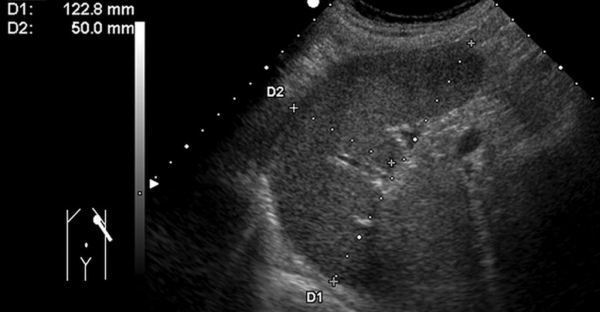

Выявить гемангиому селезенки можно после обследования на УЗИ или МРТ.

Выявить гемангиому несложно, она легко просматривается и на УЗИ и на МРТ, но часто остается скрытой, потому что имеет неярко выраженные симптомы и мало беспокоит больного. Если ее все-таки обнаружили, то чтобы подтвердить диагноз и выяснить вид новообразования, назначают ряд анализов, таких как анализ крови и костного мозга, биопсия, компьютерная томография. Ангиография — метод исследования, при котором в кровь вводится вещество, формирующее контрастное изображение на мониторе. Так можно получить самое четкое изображение новообразования и его строения.